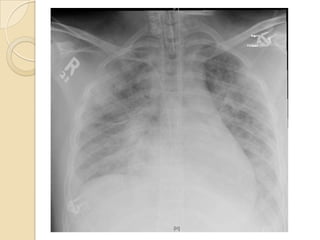

 At the Start, Subtle reticular or ground

glass opacities, often with Kerley B

lines

 Small pleural effusions are common

   Diffuse pulmonary opacities on chest

radiograph

Imaging  At theStart, Subtle reticular or ground glass opacities, often with Kerley B lines  Small pleural effusions are common

AEP is adiagnosis of exclusion and Requires :  An acute febrile illness of short duration (usually less than one week)  Hypoxemic respiratory failure  Diffuse pulmonary opacities on chest radiograph  BAL eosinophilia >25 percent  Lung biopsy evidence of eosinophilic infiltrates (acute and/or organizing diffuse alveolar damage with prominent eosinophilia is the most characteristic finding)  Absence of known causes of eosinophilic pneumonia, including drugs, infections.